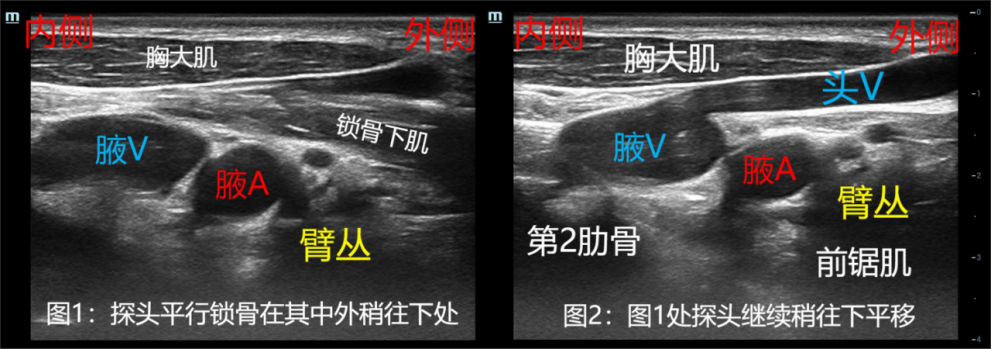

上图为扫查时不加压的图像,静脉显示清楚。上图中从图1到图2,可观察到表浅的锁骨下肌消失,下方的前锯肌出现。该图重点观察头静脉汇入腋静脉,穿刺时注意避开。